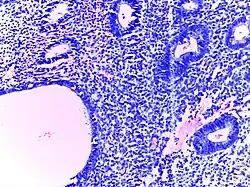

![]() | Lymph node metastasis | Lymph node showing metastases from colorectal carcinoma | Category: Lymph node metastases | Lymph node metastasis |